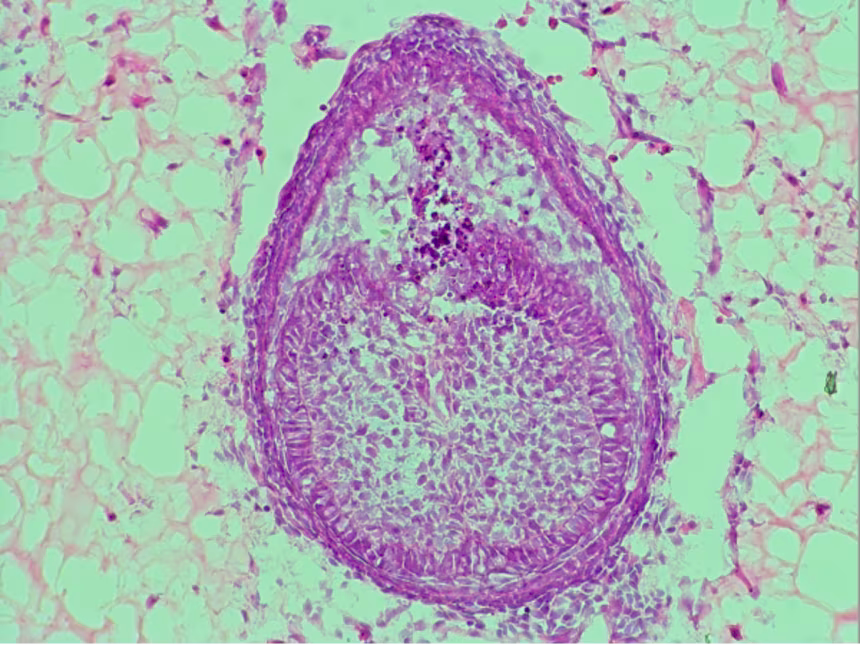

Esse material é um tipo de polímero com alto teor de água, que funciona como uma “casinha” para o desenvolvimento das células, simulando o ambiente real da boca humana. Segundo Xuechen Zhang, doutorando e coautor do estudo, o processo envolve misturar células embrionárias de camundongos e deixá-las crescer por cerca de oito dias dentro do hidrogel. No final, o resultado é impressionante: pequenas estruturas semelhantes a dentes, chamadas de primórdios dentários, surgem espontaneamente.

Essa inovação supera o método anterior, que usava colágeno e não oferecia o mesmo nível de suporte às células. O novo material permitiu um diálogo celular mais eficiente — um verdadeiro “bate-papo biológico” no qual as células trocam sinais que as orientam a formar esmalte, dentina e raiz.